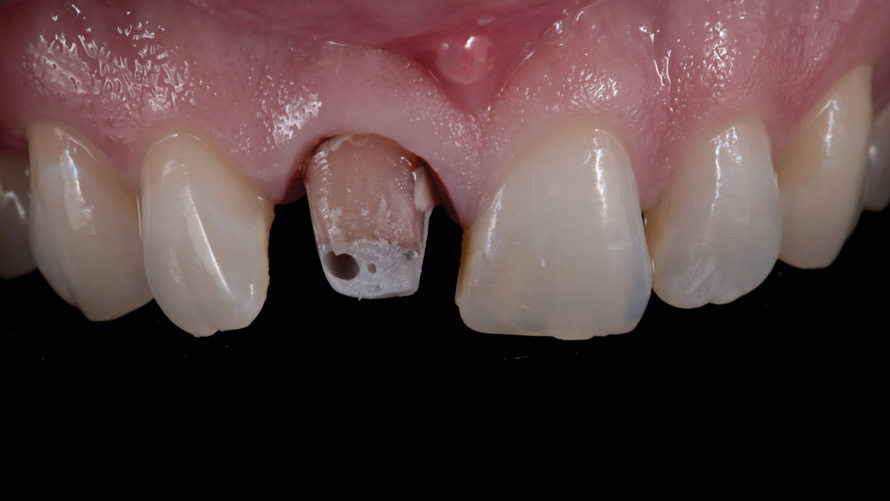

The prosthetic and endodontic protocols were nearly identical for all phases of treatment in both cases. At the first operative visit, the existing ceramic crown was carefully sectioned and removed (Figure 5 and Figure 6). This was followed by the removal of any existing supragingival core materials in the first case. Next, the highly chromatic underlying natural stump shade was recorded, and a provisional restoration was fabricated and luted with temporary cement. Each patient was then immediately dismissed to the endodontist for same-day elective root canal therapy and internal bleaching treatment with the walking bleach technique.

(5.) Case 1: Discolored stump and resin core immediately following sectioning and removal of the existing ceramic restoration.

Figure 5